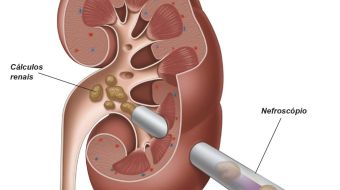

Cirurgia renal percutânea

Uma punção do rim com agulha fina permite uma dilatação de um trajeto da pele até a cavidade intra-renal. Um aparelho endoscópico (nefroscópio) é introduzido por uma bainha deixada neste trajeto. Por esse nefroscópio são introduzidos litotritor para fragmentação do cálculo e pinças para retirada de fragmentos. Apresenta-se como modalidade de maior índice de sucesso para tratamento de cálculo renal maior que 1,5 cm, independentemente da localização, composição ou anatomia renal.